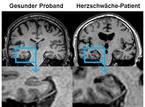

Ein Würzburger Forscherteam hat jetzt bestätigt, dass 41 Prozent der untersuchten Herzschwäche-Patienten Defizite in der Reaktionszeit aufwiesen, 46 Prozent Defizite im verbalen Gedächtnis. Im Kopf-MRT zeigten die Patienten im Vergleich zu herzgesunden Normalpersonen eine stärkere Atrophie des Temporallappens, der eine wichtige Rolle für die Gedächtnisbildung innehat.

Neben der zügigen und aufwändigen Evaluation unterscheidet Cognition.Matters-HF noch etwas von bisherigen Herz-Hirn-Studien. „Um die MRT-Bilder unserer Herzschwäche-Patienten auszuwerten, haben wir die Bilder mit insgesamt 288 gesunden Probanden gleichen Geschlechts und Alters aus einer Österreichischen Schlaganfall-Studie verglichen. „Ohne die Kooperation mit Professor Reinhold Schmidt aus der Grazer Universitätsklinik für Neurologie hätten wir nicht solche aussagekräftigen Hinweise für eine Verbindung zwischen insuffizienten Herzen und kognitiven Defiziten und Veränderungen im Gehirn erhalten“, bedankt sich Professor Stoll, leitender Oberarzt der Neurologischen Klinik und Poliklinik am Uniklinikum Würzburg.

„Mit dieser wegweisenden Studie haben wir die Hypothese weiter untermauert, dass das schwache Herz die Gehirnfunktion beeinträchtigt und insbesondere Auffälligkeiten im Temporallappen als wahrscheinliche Ursache identifizieren können. Interessanterweise waren die häufig angeschuldigten Läsionen in der weißen Substanz des Gehirn bei den Herzinsuffizienzpatienten und dem Kontrollkollektiv gleich stark ausgeprägt“.